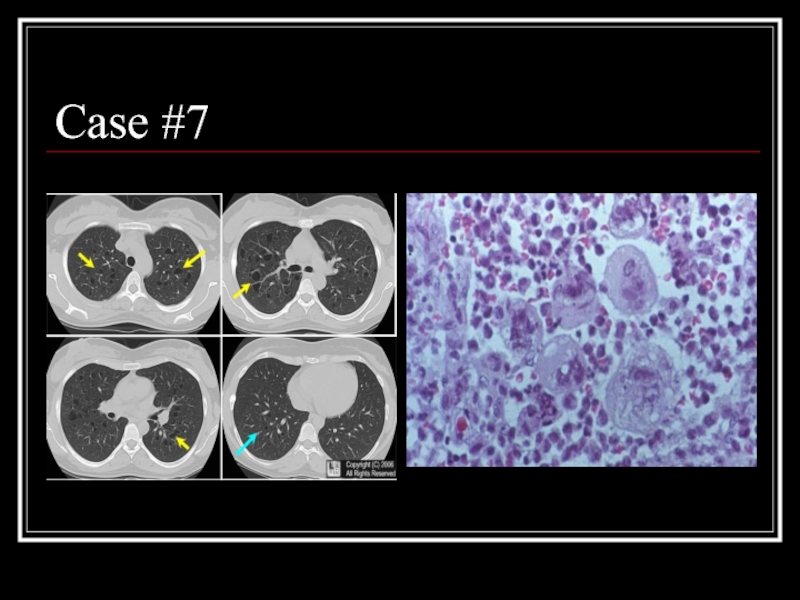

Слайд 31Case #7

Слайд 32Answer: PLCH

CT: multiple small, irregularly-shaped, cysts of varying sizes with thin

walls scattered throughout the lungs (yellow arrows) relatively sparing the bases

Path: eosinophilic granuloma